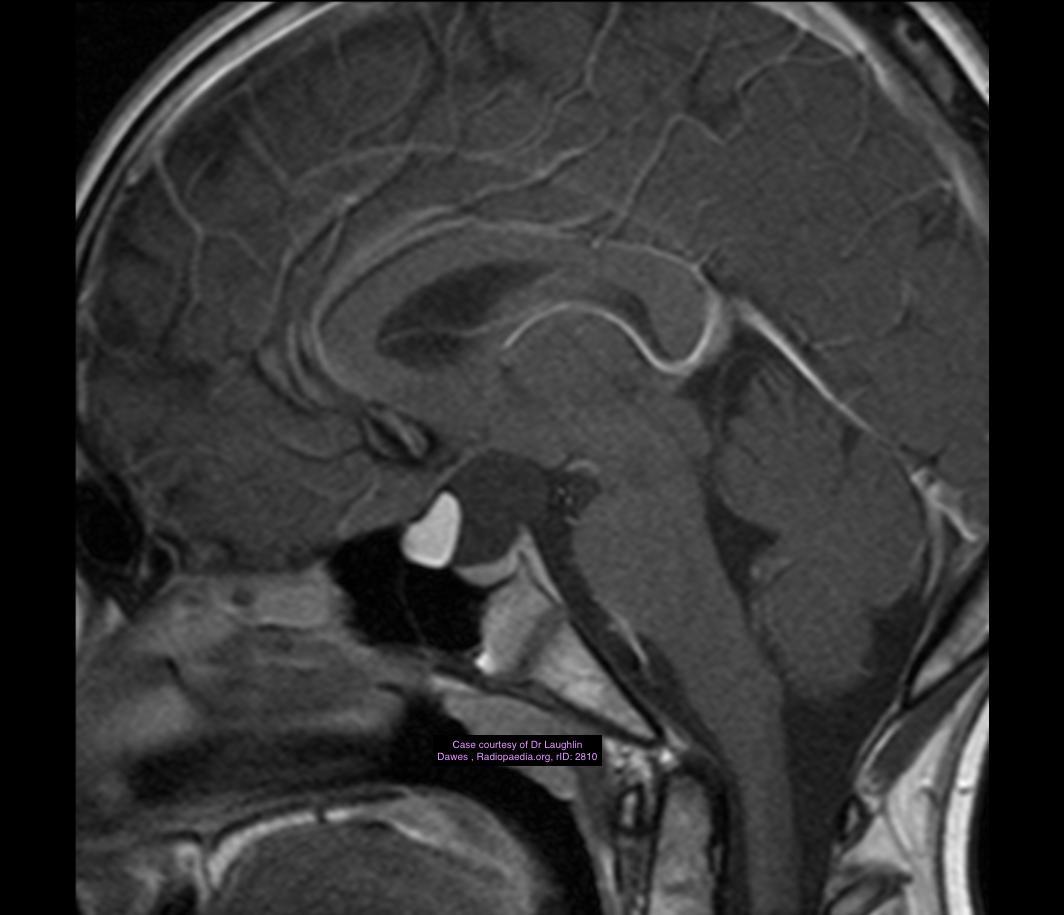

This sagittal T1-weighted MR image shows a suprasellar lesion in a 12 year-old boy. There is a fat-containing area and a cystic area. There was minimal soft tissue component. The lesion expanded and remodelled the sella, without bone erosion. There is elevation of the optic chiasm, and the pituitary can be seen compressed into the base of its fossa.

Case Discussion

The lesion was biopsied. There were epithelial elements, underlying connective tissue with sebaceous glands, and fat, consistent with a mature teratoma. There were no immature or malignant components.

Intracranial teratomas are midline tumours which may contain calcium, soft tissue, cysts and fat. They occur from the optic chiasm to pineal regions. They may be mature, immature or malignant, depending on the degree of differentiation. Differential diagnoses include craniopharyngioma, dermoid and non-germinoma germ cell tumour.